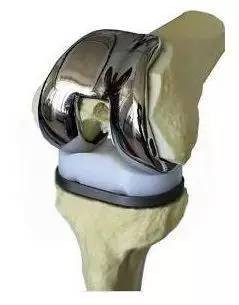

现在通过大量研究和临床实践证实,人工关节等钛和钴铬钼合金材质的骨科金属植入物不仅在核磁共振里是安全的,而且核磁共振还能专门针对关节假体进行评估,发现很多引起手术后疼痛的原因,为骨科手术病人保驾护航。这些成果推翻了金属不能进核磁共振的既定结论。“大型微波炉”终于迎来了翻身的日子。